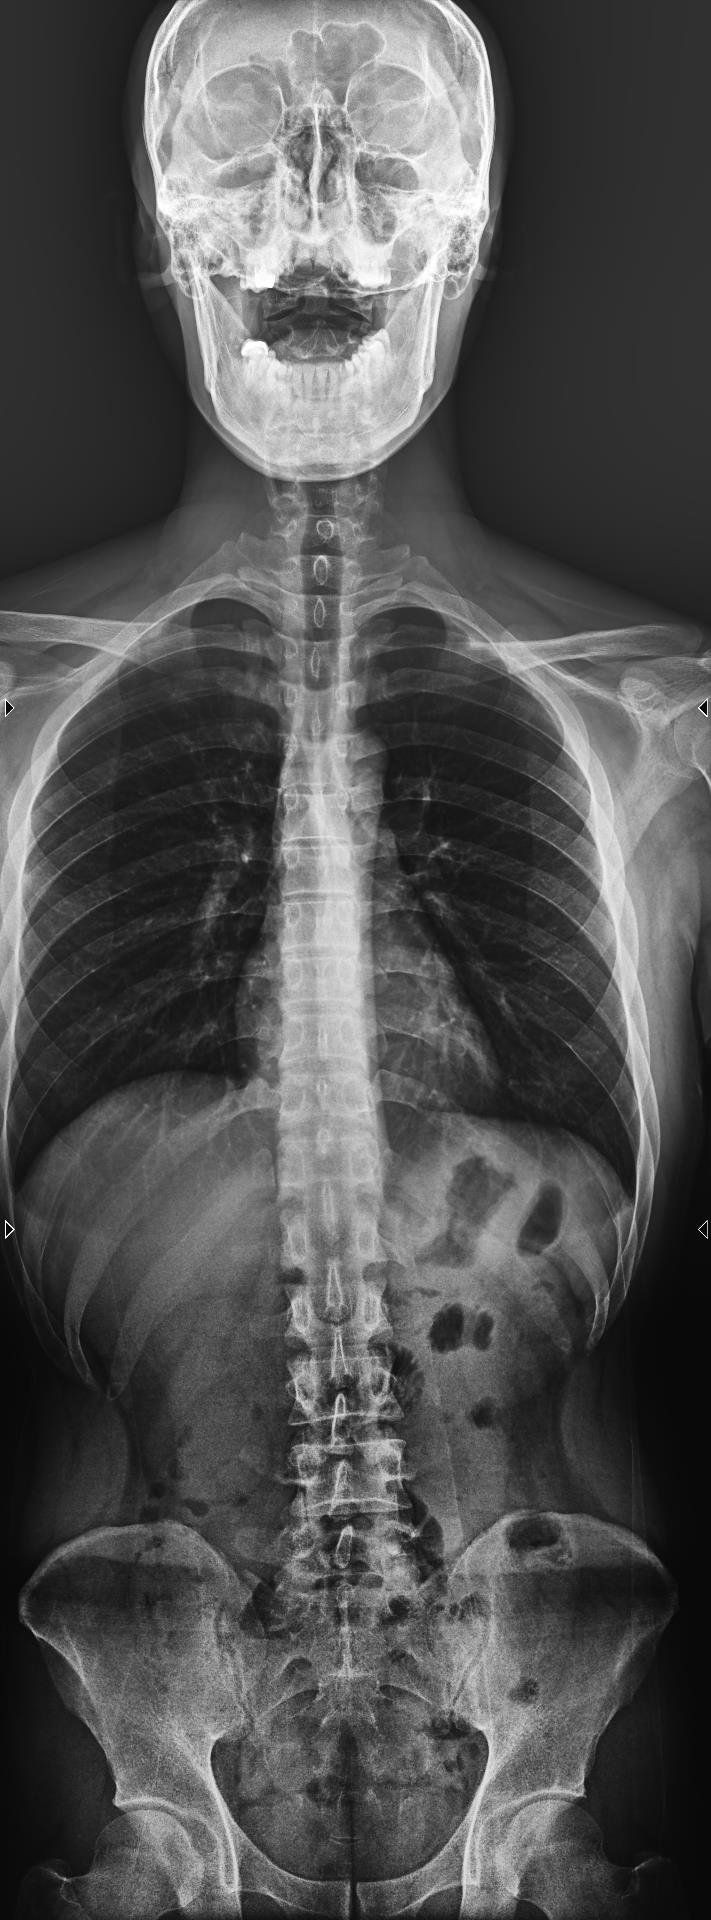

Ảnh chụp X-Quang cột sống (ảnh trên: một phần, ảnh dưới: toàn phần)

Chụp X-quang cột sống là kỹ thuật sử dụng tia X để ghi lại hình ảnh cấu trúc xương của cột sống, bao gồm các đốt sống cổ, ngực, thắt lưng và xương cùng. Với X-quang cột sống toàn phần, bác sĩ có thể quan sát cột sống như một chỉnh thể thống nhất, thay vì chỉ nhìn từng đoạn riêng lẻ.

Chụp X-quang toàn bộ cột sống là phương pháp chẩn đoán hình ảnh giúp bác sĩ đánh giá tổng thể cấu trúc xương sống, từ đó phát hiện sớm nhiều bất thường và bệnh lý quan trọng. Thay vì chỉ quan sát từng đoạn riêng lẻ, kỹ thuật này cho phép nhìn cột sống như một chỉnh thể thống nhất, phản ánh đúng trục chịu lực và sự liên kết giữa các vùng cổ – ngực – thắt lưng – xương cùng.

Hình ảnh X-quang toàn bộ cột sống được ghi nhận ở nhiều tư thế, nhiều góc độ, giúp bác sĩ: